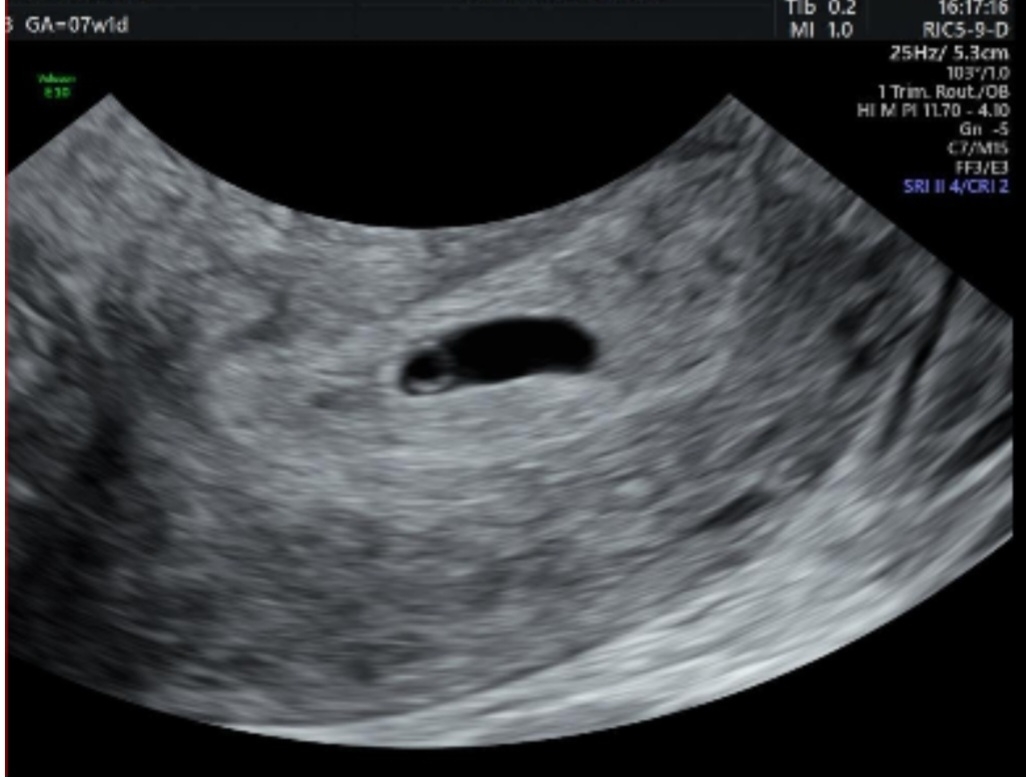

첫만남 😍

드디어 첫 초음파 하고 왔어요. 근데 제가 생리주기가 불규칙하고 길어서 평균 35일쯤 되서, 주수 차이가 많이 나네요.. 앱으로는 7주2일차였는데 태아 사이즈 보니 5주2일쯤 되는것 같다고... 잘 크고 있는거겠죠? ㅠㅠ 그래도 아기집도 보고 난황도 보고 와서 기뻐요. 2주뒤에 다시 초음파 보자고 예약하고 왔어요. 2주뒤엔 심소도 듣고 왔으면 좋겠네요..